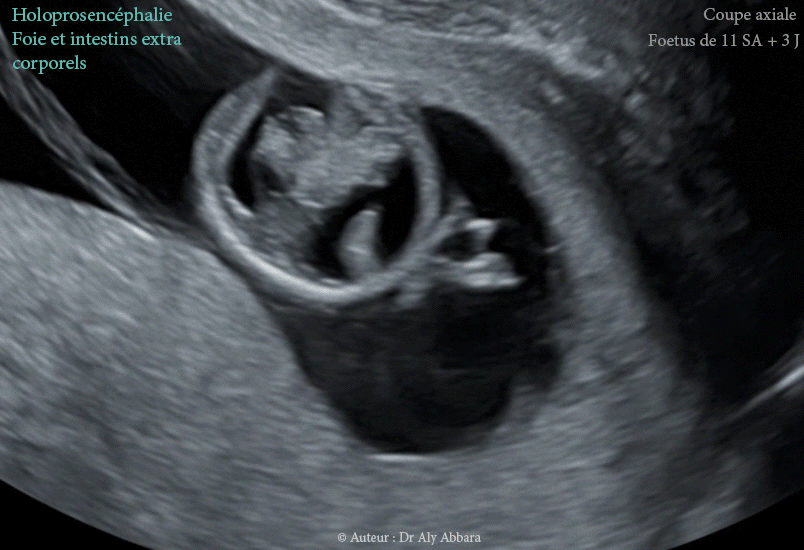

Séquences échographiques montrant, chez un fœtus de 11 SA et 3 jours (LCC = 48 mm), la présence d'une holoprosencéphalie d'après les éléments malformatifis suivants :

• Ce fœtus présente d'autres anomalies (syndrome polymalformatif), en particulier, une célosomie (défaut de la fermeture la paroi abdominale ventrale) avec l'extériorisation complète du foie hors de la cavité abdominal et une laparoschisis (intestins grêles en position extra-abdominle).